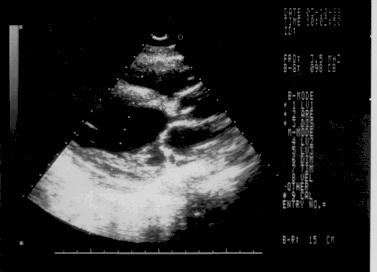

Подклапанный стеноз аорты дискретный мембранозный

Сразу под клапаном аорты расположена тонкая фиброзная мембрана (рис.95).

Рис.95.

1. Фиброзная мембрана сразу под аортальным клапаном, пролабирующая в выходной тракт левого желудочка в диастолу (рис.96).

2. Узкий выходной тракт левого желудочка.